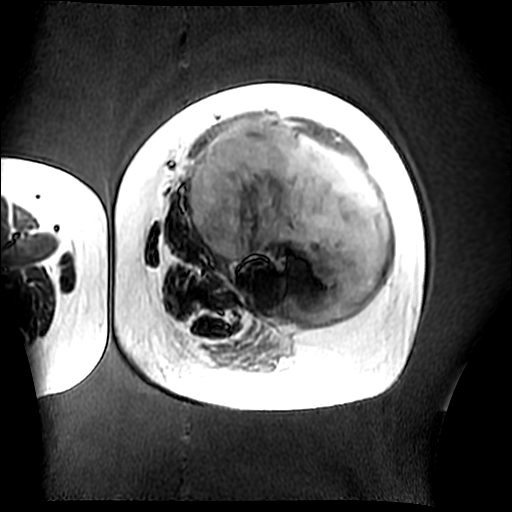

左侧大腿外伤10余年,当时情况不清,发现左侧大腿肿胀7年余,而后又有多次外伤史,近1年来出现疼痛,减重半年。查体:左侧大腿肿胀明显,皮温、肤色正常。

增强

软组织肿块,股骨破坏,增强不均匀强化-----支持恶性肿瘤